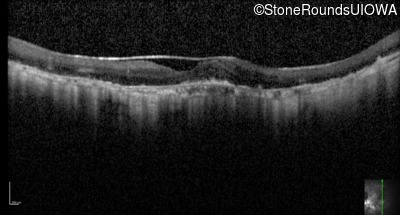

Optical Coherence Tomography - Left - 10/32 -2

Exemplar / OCT Stack

OCT Stack